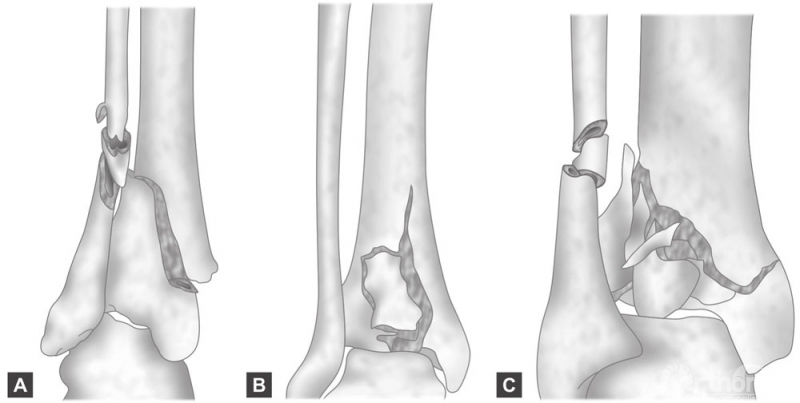

AO/OTA的分型如下(图3A~C):

图3 A~C

A型:关节外的骨折,又分为三个亚型:简单(A1),粉碎(A2),严重粉碎(A3);

B型:只涉及一部分关节面和一柱,分为三个亚型:单纯的劈裂骨折(B1),劈裂伴有塌陷(B2),有塌陷和多发的骨折碎片(B3);

C型:涉及整个骨关节面,分为三个亚型,关节面和干骺端裂隙(C1),简单关节裂隙伴有干骺端粉碎性骨折(C2),关节面和干骺端的粉碎性骨折(C3)。